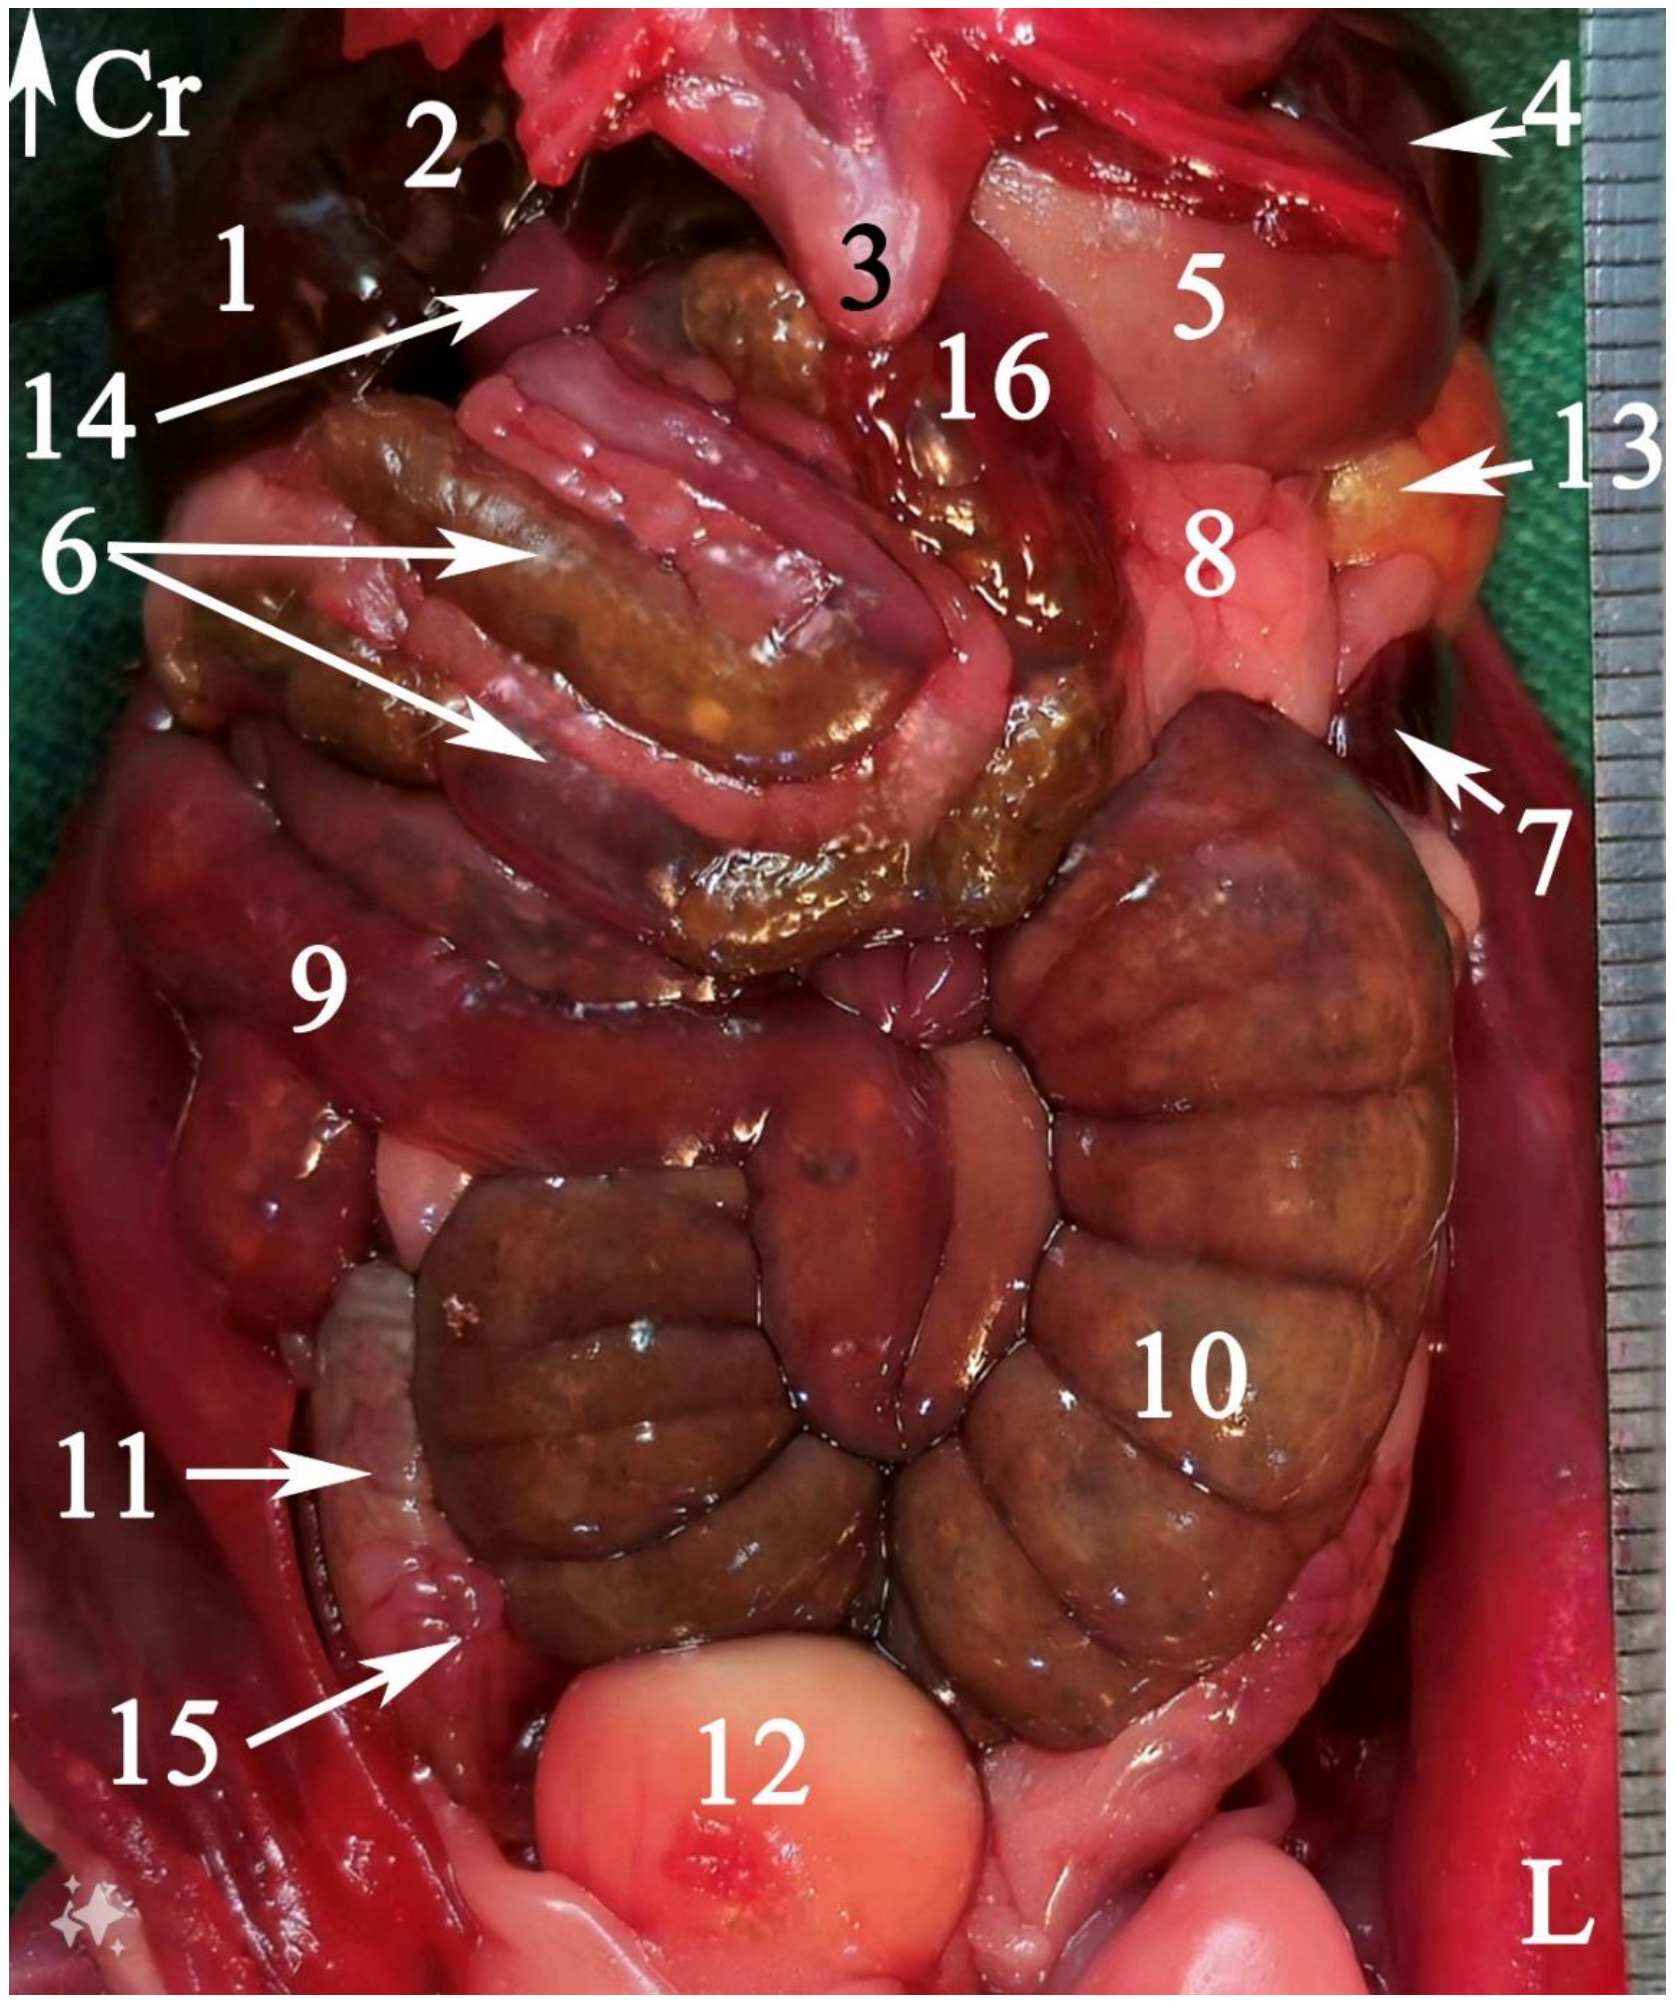

3.1. Topographic Anatomy

2.5.1. Topographic Anatomy